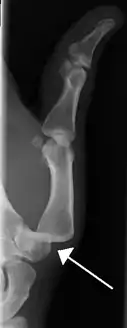

Dislocation of the left index finger

Radiograph of right fifth phalanx bone dislocation

Radiograph of left index finger dislocation

Radiograph of right fifth phalanx dislocation resulting from bicycle accident

Right fifth phalanx dislocation resulting from bicycle accident